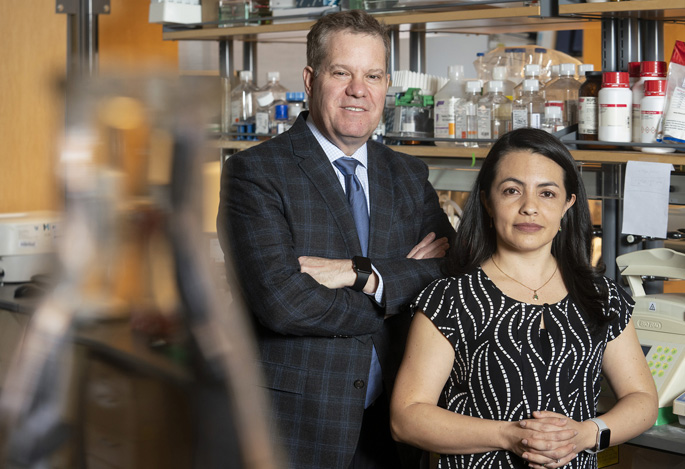

“H. pylori has co-evolved with humans for at least 60,000 years, probably longer, and attempting to prevent stomach cancer by eliminating the infection with widespread use of antibiotics is not necessarily a good idea,” said Keith Wilson, MD, Thomas F. Frist Sr. Professor of Medicine and professor of Pathology, Microbiology and Immunology.

“Our study suggests that it might be possible to reduce the virulence of the bacteria, without having to eliminate it. It’s a speculative and unusual way to think about an infection, but it could be an interesting strategy.”

Wilson, who also directs the Vanderbilt Center for Mucosal Inflammation and Cancer, and his team previously linked the production of cell growth compounds called polyamines to the development of stomach cancer in an H. pylori-infected animal model. They demonstrated that treatment of the animals with DFMO, which inhibits an enzyme that is key to the production of polyamines, prevents stomach cancer.

To further explore how DFMO works, J. Carolina Sierra, PhD, research instructor in Medicine, collected H. pylori bacteria from infected animals that had been treated (or not) with DFMO. Using an in vitro test, she assessed the activity of one of the main H. pylori virulence factors, a protein called CagA. CagA is “injected” into stomach epithelial cells, where it contributes to oncogenic signaling pathways.

“What we noticed is that bacterial strains coming from DFMO-treated animals have reduced ability to move this virulence factor into epithelial cells,” Sierra said.

This finding, Wilson said, supports using DFMO or other tools to reduce H. pylori virulence for cancer prevention.

“This drug (DFMO), which inhibits a very specific enzymatic pathway, also has what some might call ‘off target’ effects: it causes mutations in an H. pylori gene that affects the translocation of CagA,” Wilson said. “The vast majority of gastric cancer is associated with strains that are CagA-positive. If this drug interferes with CagA activity, that’s an added bonus.”

The investigators will analyze H. pylori strains isolated from the DFMO trial participants in Honduras and Puerto Rico to determine if there is a similar reduction of bacterial virulence in people.